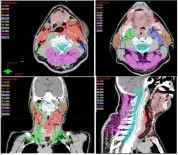

27 Ağustos 2018 Pazartesi 09:47:09Kanser Tedavisinde 'Yapay Zeka' Başarısı

Radyasyon Onkolojisi Prof. Dr. Ali Aydın Yavuz, ‘Yapay Zeka’ uygulamalarının kanserde radyoterapi tedavi başarısını arttırdığını, Yapay Zeka uygulamalarının önümüzdeki yıllarda kanser tedavilerine ciddi damga vuracağını ileri sürdü.